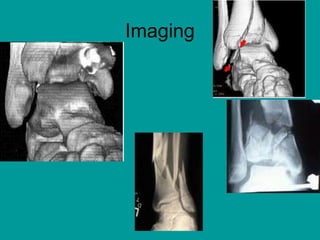

Imaging

• Routine views including AP, lateral, and

mortise views are usually adequate .

• Pilon fractures often require a computed

tomography (CT) scan to fully delineate

the extent of injury

• Radiographic views (anteroposterior [AP],

lateral, Harris views)

• Computed tomography (CT) has become

routine to fully delineate the extent of

fractures.CT is especially useful to the

surgeon planning operative intervention.

Plain radiographs alone fail to identify the

degree of fracture extension in almost half

of cases